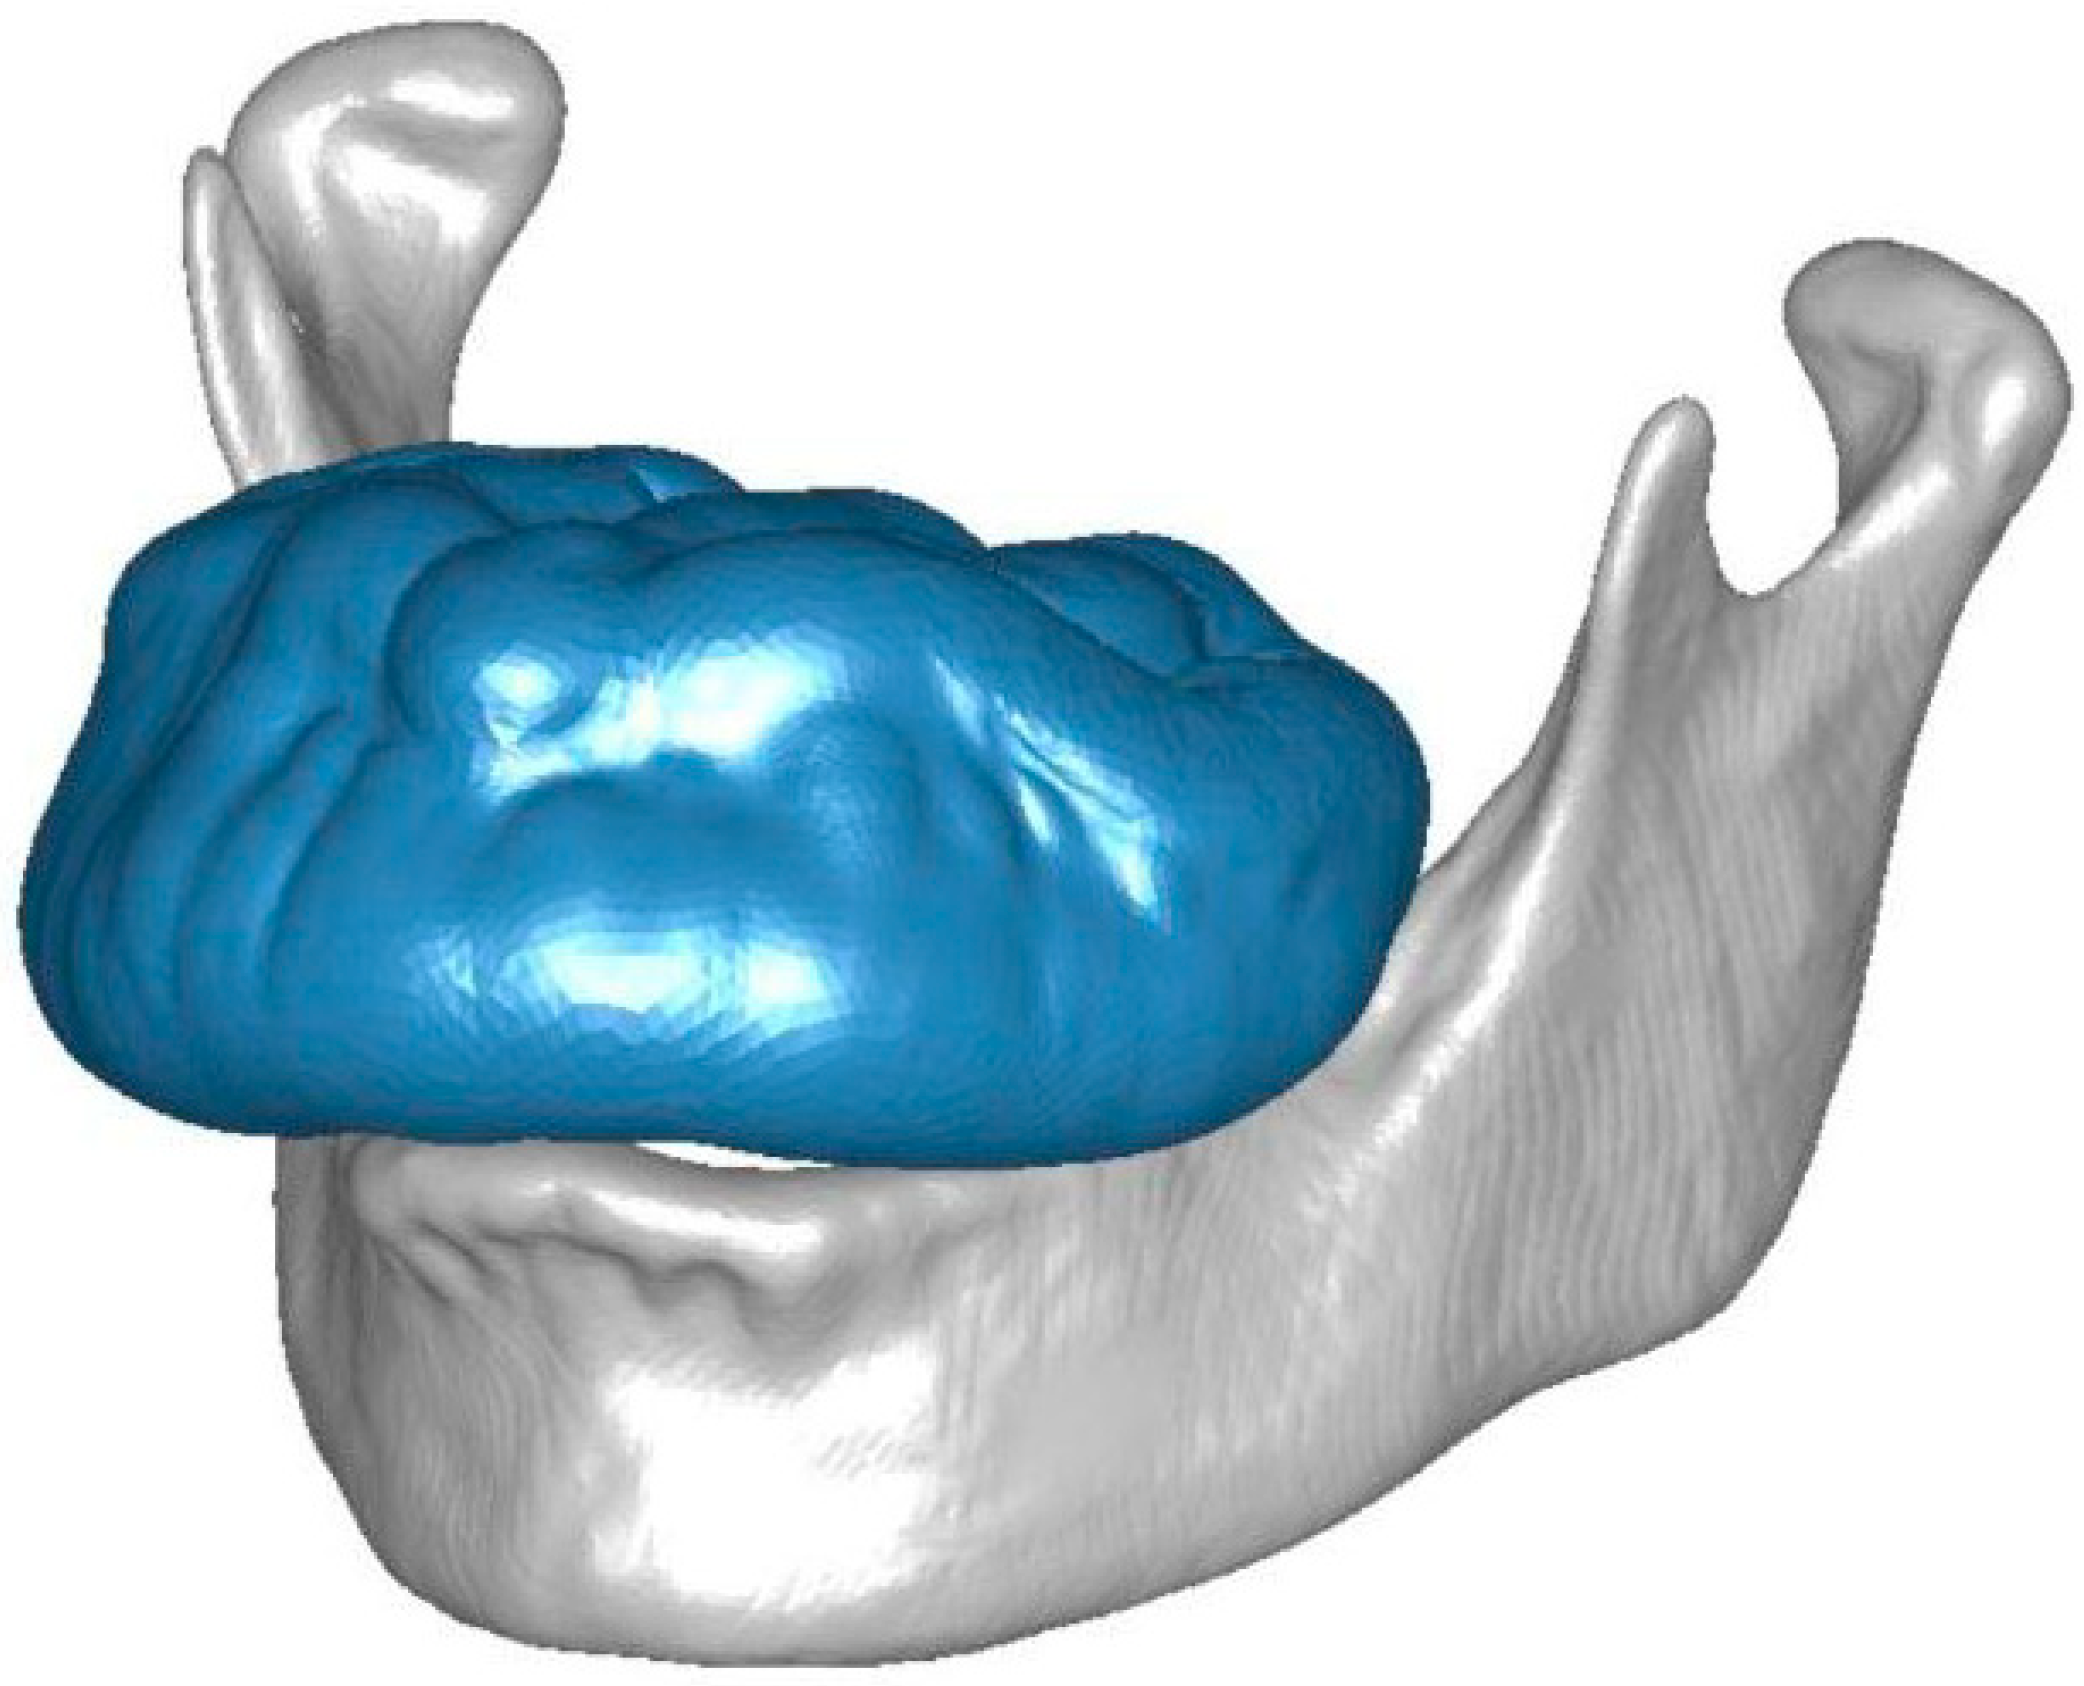

2.2. Case Study of a Maxillary Exostosis: Congruence and Contact Evaluation